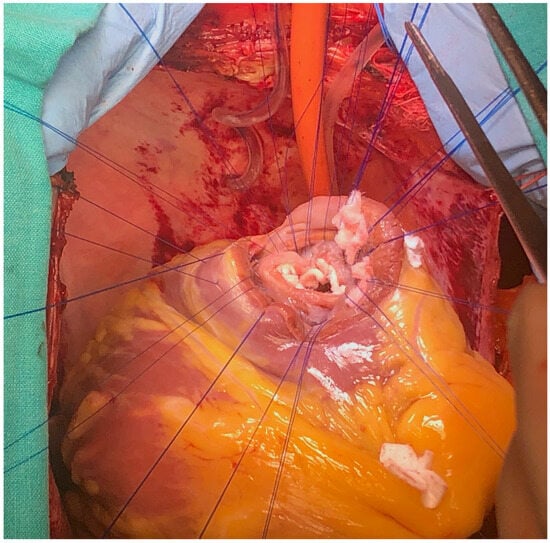

The surgery was carried out under general anesthesia, with iv induction and inhaled sevoflurane maintenance and total iv anesthesia during CPB. After median sternotomy, bicaval CPB was started, and the heart was arrested using anterograde and retrograde cold blood cardioplegia. After snaring both venae cava, the heart was enucleated with a 3.0 polypropylene stitch at the apex. A 10 cm incision was made on the posterior surface of the left ventricle, 2 mm parallel to the posterior interventricular artery. The margins of the VSD were identified. Interrupted matrass sutures of 2.0 Tevdek were placed circumferentially around the defect and used to secure a 4 × 7 cm bovine pericardial patch. The posterior papillary muscle was retracted into the sutures, so the mitral valve was replaced with a 27 biological prosthesis with preservation of the sub-valvular apparatus. The left ventriculotomy was closed with a double layer surjet suture, reinforced with Teflon felts. Details with surgical technique are shown in Figure 5, Figure 6, Figure 7 and Figure 8.

Figure 7. Surgical technique detail—VSD suture finished.

Figure 8. Intraoperative technique showing VSD repair with bovine pericardial patch (surgical technique described in text).